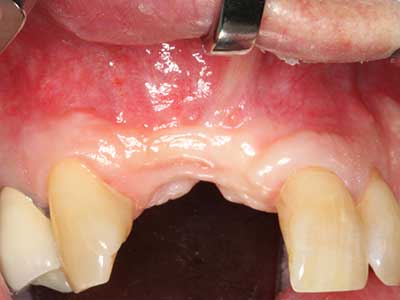

Aplicación: Terapia periodontal

En pacientes de edad avanzada, las enfermedades periodontales marginales representan la razón principal por la que es preciso realizar una extracción. Estas enfermedades tienen principalmente su causa en una colonización bacteriana de la bolsa periodontal y en la inflamación que esta provoca, lo que da lugar a una pérdida del ligamento periodontal. La formación de biopelículas y concreciones subgingivales representa un factor etiológico decisivo para la degradación ósea marginal, por lo que su eliminación cobra una importancia especial en la terapia (Drisko 2014, Plessas 2014).

En el tratamiento de una periodontitis se hace una diferenciación entre la fase inicial y la fase quirúrgica. Además de la instrucción y la motivación entorno a la higiene bucal, en ambas fases debe realizarse una limpieza apropiada de la superficie radicular; a este respecto, en el tratamiento regenerador se elige casi siempre un acceso abierto. La superficie radicular también puede limpiarse mediante piezocirugía utilizando piezas especiales, pues el uso de insertos de diferentes curvaturas permite llegar a zonas de difícil acceso, como son las furcaciones. En esta técnica, la refrigeración interna de agua del sistema ayuda a retirar las concreciones y las bacterias disueltas de la bolsa periodontal. Por otro lado, para reducir a un mínimo la eliminación de la sustancia dental dura, en los sistemas especiales como el Piezomed se ha incorporado una aplicación con retroalimentación. En este caso, según se ejerza más presión sobre la pieza periodontal, la potencia de eliminación se reduce.